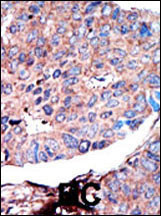

Formalin-fixed and paraffin-embedded human cancer tissue reacted with the primary antibody, which was peroxidase-conjugated to the secondary antibody, followed by AEC staining. This data demonstrates the use of this antibody for immunohistochemistry; clinical relevance has not been evaluated. BC = breast carcinoma; HC = hepatocarcinoma.

Formalin-fixed and paraffin-embedded human breast carcinoma tissue reacted with GSK3A Antibody (N-term) (Cat. APR12316G), which was peroxidase-conjugated to the secondary antibody, followed by DAB staining. This data demonstrates the use of this antibody for immunohistochemistry; clinical relevance has not been evaluated. |